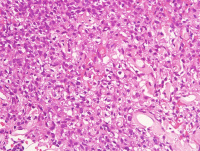

左颊黏膜肿物

性别

女

年龄

63岁

发现左颊黏膜肿物半个月,无明显疼痛

肿物1.5*1.5*1cm,界清,切面实性,红褐色,质软

图4